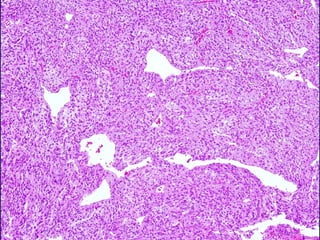

Variedades (50% o mas del tumor)

• WHO grado I (90%)

Meningoendotelial

Fibroso (Fibroblástico)

Transicional (mixto)

Psamomatoso

Angiomatoso

Microquístico

Secretor

Linfoplasmocítico

Metaplásico

MENINGIOMA ATÍPICO

• Incremento de la actividad mitótica (4 ó más x

10 HPF) o tres o más de los siguientes cuadros

• Incremento de la celularidad

• Células pequeñas con un alto ratio

nucleo:citoplasma

• Nucleolo prominente

• Patrón en mantos

• Necrosis espontanea o geografica

• Se considerara también

atípico a la combinación

de hipercelularidad con

5 o más mitosis x 10

HPF